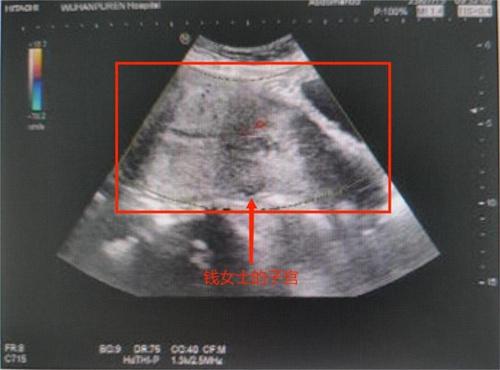

38歲的錢女士以為自己是例假不調(diào)不到,前幾日在家中自己排出一個(gè)巴掌大的肉團(tuán)。急忙趕到武漢市普仁醫(yī)院產(chǎn)科就醫(yī),發(fā)現(xiàn)自己已經(jīng)流產(chǎn)了,痛失了自己在腹中的寶寶,感覺到極為后悔。

之前已經(jīng)切除過(guò)一邊輸卵管,加上個(gè)人有點(diǎn)胖,肚子也看不出來(lái),沒辦法想到自己已經(jīng)又懷孕了,之前僅僅以為是月經(jīng)不調(diào),由于錢女士宮腔中仍然有胎盤,還沒有清理排出,婦產(chǎn)科醫(yī)生也為錢女士安排了無(wú)痛清宮的手術(shù)。目前僅僅是在整個(gè)恢復(fù)情況上是良好的,由于肥胖對(duì)于女性,卵巢以及身體功能會(huì)產(chǎn)生影響,所以患者對(duì)自己兩次出血是先兆流產(chǎn)的表現(xiàn)也不清楚誤以為是月經(jīng)不調(diào)導(dǎo)致的。如果早點(diǎn)前往醫(yī)院檢查,并且科學(xué)不要配合治療后,孩子是完全可以等到足月分娩下來(lái)的。